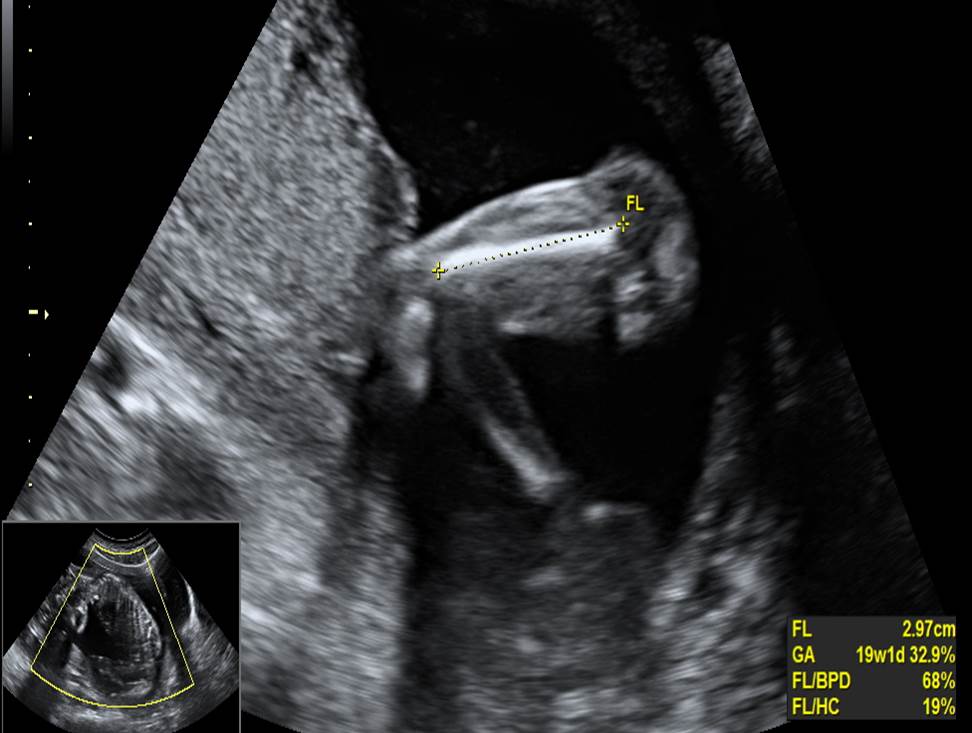

- Проанализируйте изображения плода в 19 недель, есть ли у него какие-либо маркеры хромосомной патологии?

- Необходимо ли рекомендовать инвазивную диагностику? Пациентке 28 лет, УЗ скрининг 1 триместра выполнен при КТР 46 мм, БХ скрининг не выполнен, риск ХА не рассчитан